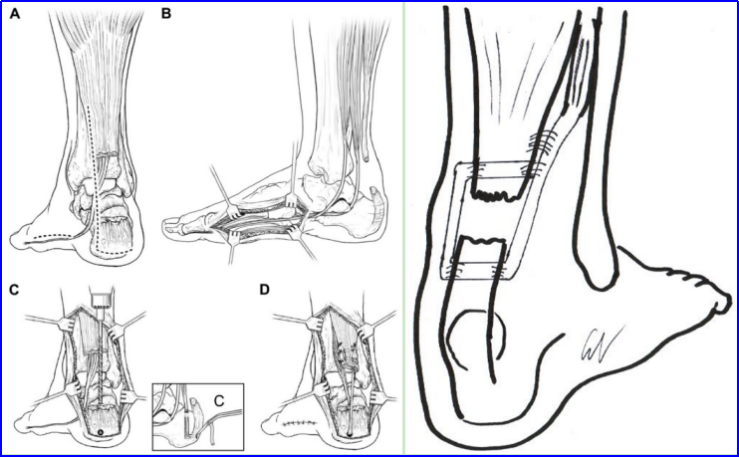

图8.(A)制作一个远端蒂皮瓣,保留1-2厘米的袖口状附着部分,其宽度为1-3厘米,长度可达12厘米。(B)然后将皮瓣游离并通过剩余的肌腱向下翻转。(C)翻转后的皮瓣能够跨越近端和远端残端之间的大缺损。(D)采用侧侧缝合的方式关闭近端取皮处的缺损和腱旁组织。使用近端和远端改良的Krackow缝合术修复翻转的皮瓣和远端残端。

图9. 示意图:2个相邻的皮瓣翻转修复。(a)利用从腓肠肌获取的内侧和外侧皮瓣重建跟腱断裂缺损。(b)跖肌肌腱加强后的重建最终视图。